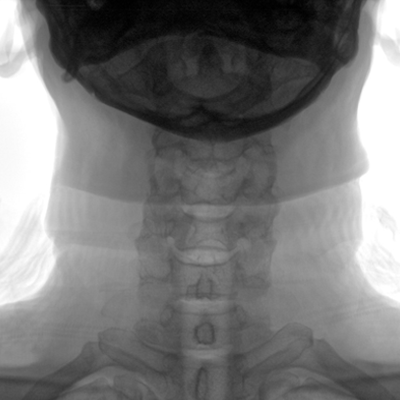

临床适用科室:骨科、普通外科、矫形外科、创伤外科、泌尿外科、脊柱外科、疼痛外科、消化科、妇科等科室。

大尺寸动态平板探测器,高DQE、低噪声、图像清晰。采用多分辨率图像增强处理技术,不同部位不同图像处理算法,满足客户多样化的需求。

图形化操控界面设计:设有多种人体特征摄影参数,操作简便。双向红光十字定位系统:实现无射线下的高效定位。信息共享:遵循DICOM3.0格式接口,可无缝对接云PACS系统。